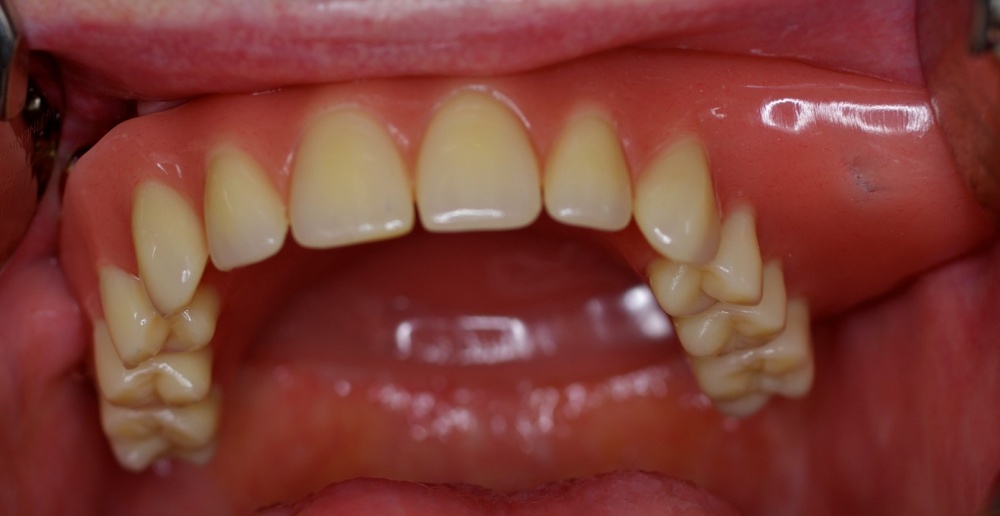

In den Ausführungen über die interdisziplinäre Zusammenarbeit der Zahnmedizin mit anderen Fachrichtungen in einem Bundeswehrkrankenhaus darf natürlich die seit vielen Jahren gewachsene und gelebte Zusammenarbeit mit der Abteilung für Mund-, Kiefer- und Gesichtschirurgie (Leiter: Prof. Dr. Dr. K.O. Henkel) im Bundeswehrkrankenhaus Hamburg nicht unerwähnt bleiben. Die Tatsache, dass beide Fachrichtungen die gleichen bzw. unmittelbar benachbarte anatomische Strukturen behandeln, führt zur einer engen Zusammenarbeit. Beispielhaft sei hier die Implantation enossaler Implantate zum Ersatz verloren gegangener Zähne erwähnt. Grundsätzlich können die Anforderungen des Zahnarztes und des Kieferchirurgen an die Implantation durchaus abweichen. Der Kieferchirurg wird überwiegend die Region zur Implantation favorisieren, die das beste Knochenangebot hinsichtlich der Höhe und Breite des Alveolarknochens bietet. Diese Position ist jedoch nicht unbedingt die beste Implantatposition im Hinblick auf die spätere Versorgung mit implantatgetragenem Zahnersatz. Zur Gewährleistung einer abgestimmten Therapie und einer auch für die prothetische Versorgung idealen Implantatstellung wurde bereits im Jahre 1993 eine gemeinsame Implantatsprechstunde eingeführt, in der sich jeweils ein Zahnarzt und ein ärztlicher Kollege der Abteilung für Mund-, Kiefer- und Gesichtschirurgie über Indikation und Machbarkeit der Insertion zahnärztlicher Implantate beraten und gegebenenfalls die entsprechende Antragstellung initiieren. Zur Vollständigkeit sei hier erwähnt, dass die Versorgung mit zahnärztlichen Implantaten grundsätzlich kein Bestandteil der uTV ist und immer der Genehmigung im Sinne einer Einzelfallentscheidung durch den Begutachtenden Zahnarzt der Bundeswehr im Kdo SanDstBw bedarf. Eine besondere Herausforderung stellt die kaufunktionelle und oral-ästhetische Rehabilitierung von Patienten mit schwierigen anatomischen Verhältnissen dar, so wie sie nach Verwundungen im Gesichtsbereich, aber auch nach Tumorerkrankungen in der Mundhöhle auftreten können. Auch hier hat sich die enge Zusammenarbeit der Abteilung für Mund-, Kiefer- und Gesichtschirurgie mit der Zahnmedizin bewährt (Abb. 5, 6, 7).